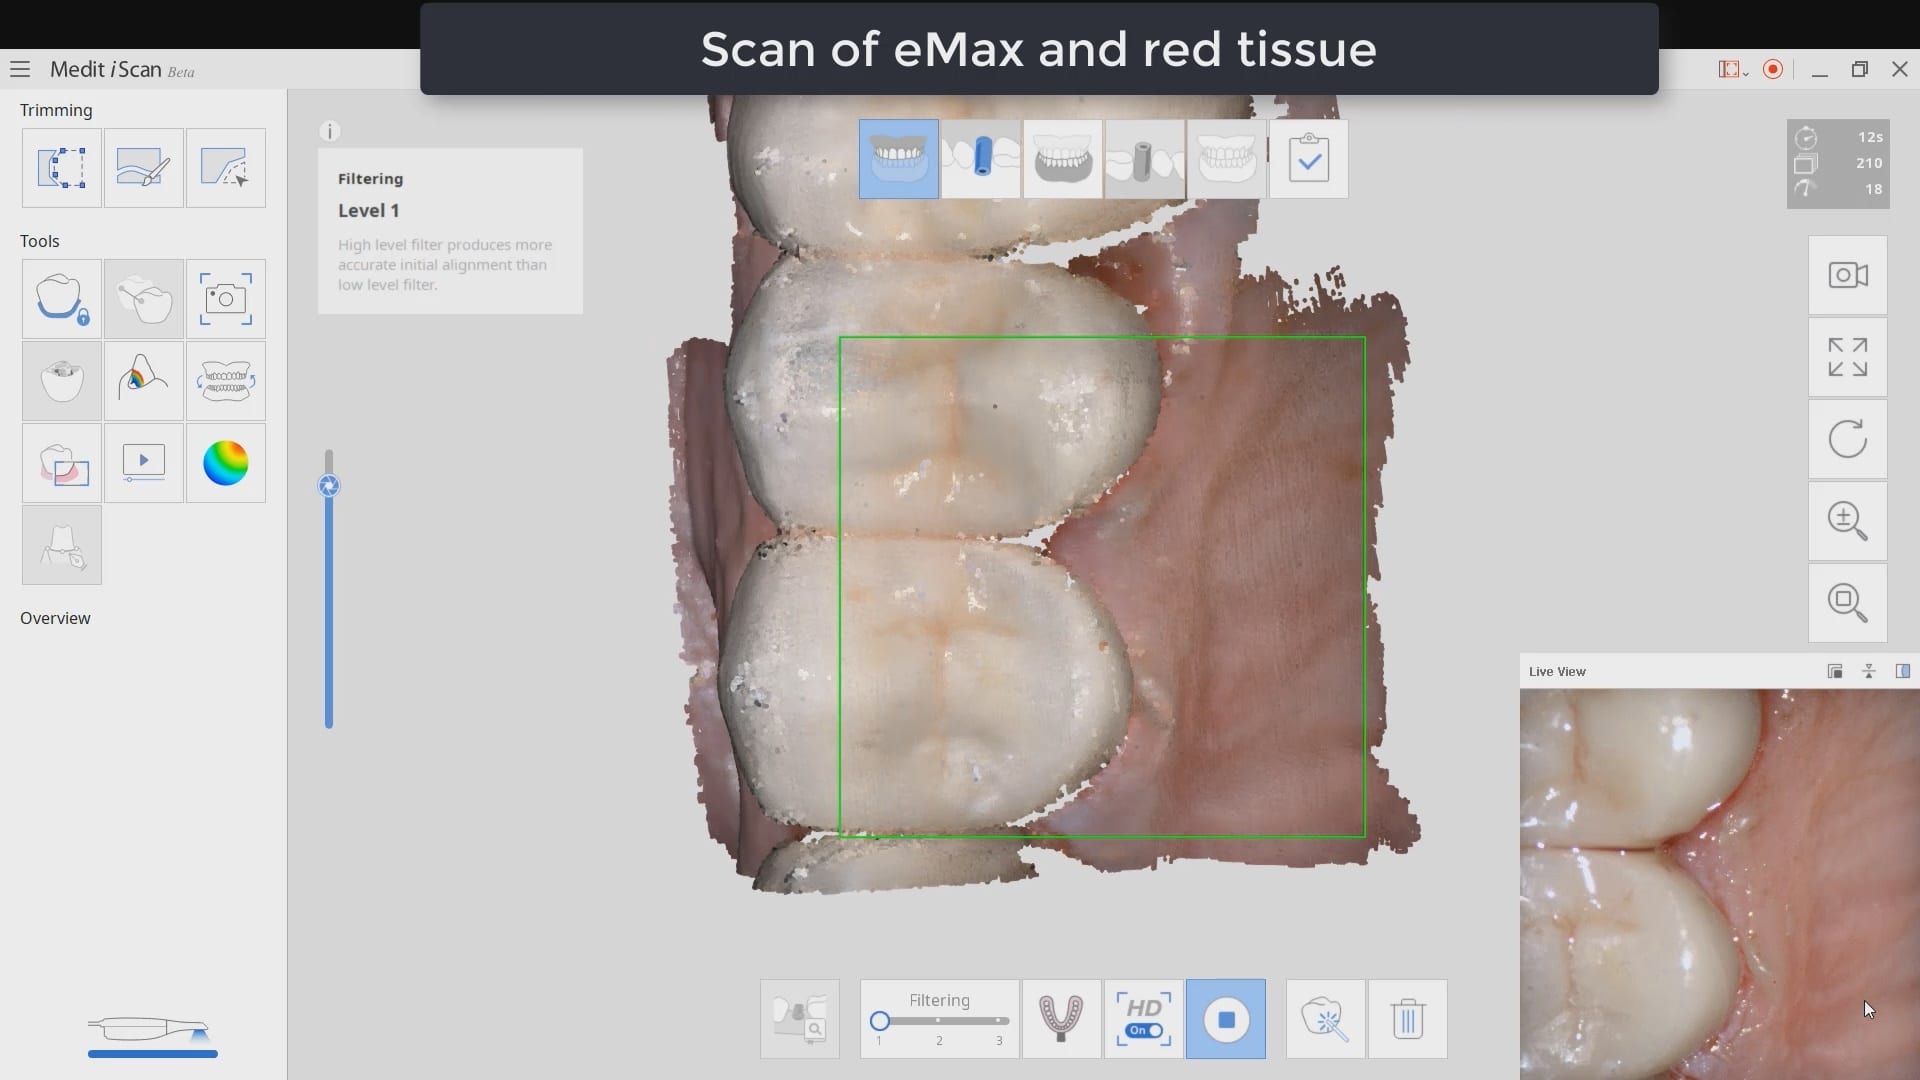

Post op intra-oral scan with Medit i500 to capture irritated and hemorrhaging tissue (for demonstration purposes only)